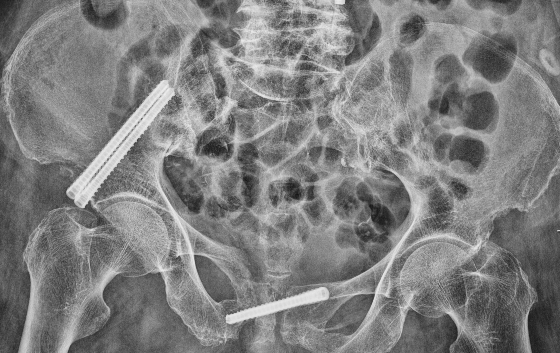

然而病情并没有家属想象中简单,检查结果显示梁婆婆右侧耻骨上下支骨折、腰椎椎管狭窄,却未发现胸腰椎新鲜压缩骨折。经冯学烽主任、杨立进主治医师查体发现,婆婆还伴有臀、腿麻木症状。